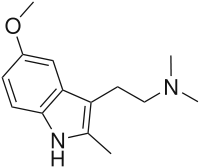

Substituted tryptamines, or serotonin analogues, are organic compounds which may be thought of as being derived from tryptamine itself. The molecular structures of all tryptamines contain an indole ring, joined to an amino (NH2) group via an ethyl (−CH2–CH2−) sidechain. In substituted tryptamines, the indole ring, sidechain, and/or amino group are modified by substituting another group for one of the hydrogen (H) atoms.

| Chemical structure | Short Name | Origin | Ring Substitution | RN1 | RN2 | Full Name | CAS Number |

|---|---|---|---|---|---|---|---|

| 2-Methyl-DMT | artificial | 2-CH3 | CH3 | CH3 | (2-(2-methyl-1H-indol-3-yl)-1-methyl-ethyl)dimethylamine | 1080-95-1 |